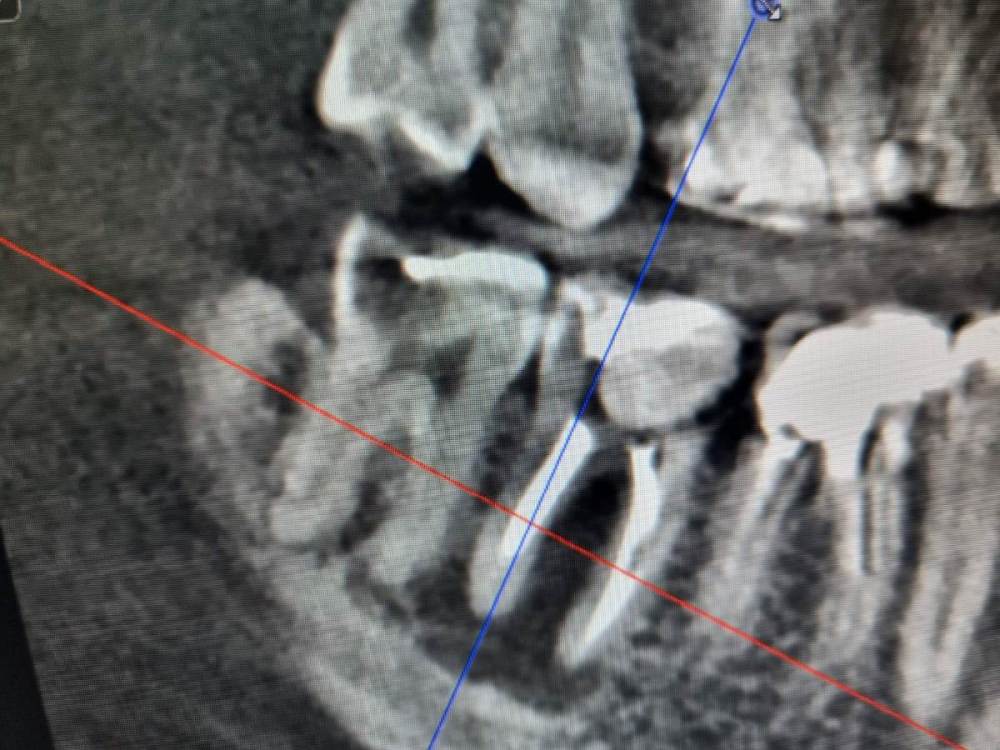

Chelovek2012 Опубликовано 15 мая, 2023 Автор Поделиться Опубликовано 15 мая, 2023 (изменено) Был сегодня у врача. 6 Верхний зуб пока запломбировал и не стал ставить имплант. Почему-то. Наверное, увидел более серьезную проблему. НО! Он сказал, что нижний 8 зуб мудрости нужно удалить. Так же 7 зуб говорит что огромная проблема. Говорит, что нужно принимать решение про удаление 8 и нижней 7ки. Два зуба. Потом 4 месяца на то, чтобы там все раросло и еще 4 месяца за работы по импланту 8 месяцев на лечение. Я не представляю, как без 7 зуба столько проходить. Уверенность в себе будет нарушена так на долго Ну и эстетика Год+ назад этого не было. Изменено 15 мая, 2023 пользователем Chelovek2012 Ссылка на комментарий

Chelovek2012 Опубликовано 15 мая, 2023 Автор Поделиться Опубликовано 15 мая, 2023 (изменено) Уже читал про имплантацию.. Возможна ли тут одномоментная имплантация 7 нижнего зуба? Или там воспалительный процесс и это нереально? Как долго можно откладывать имплантацию? Можно ли вылечить воспаление в этом зубе, чтобы его сохранить? Изменено 16 мая, 2023 пользователем Chelovek2012 Ссылка на комментарий